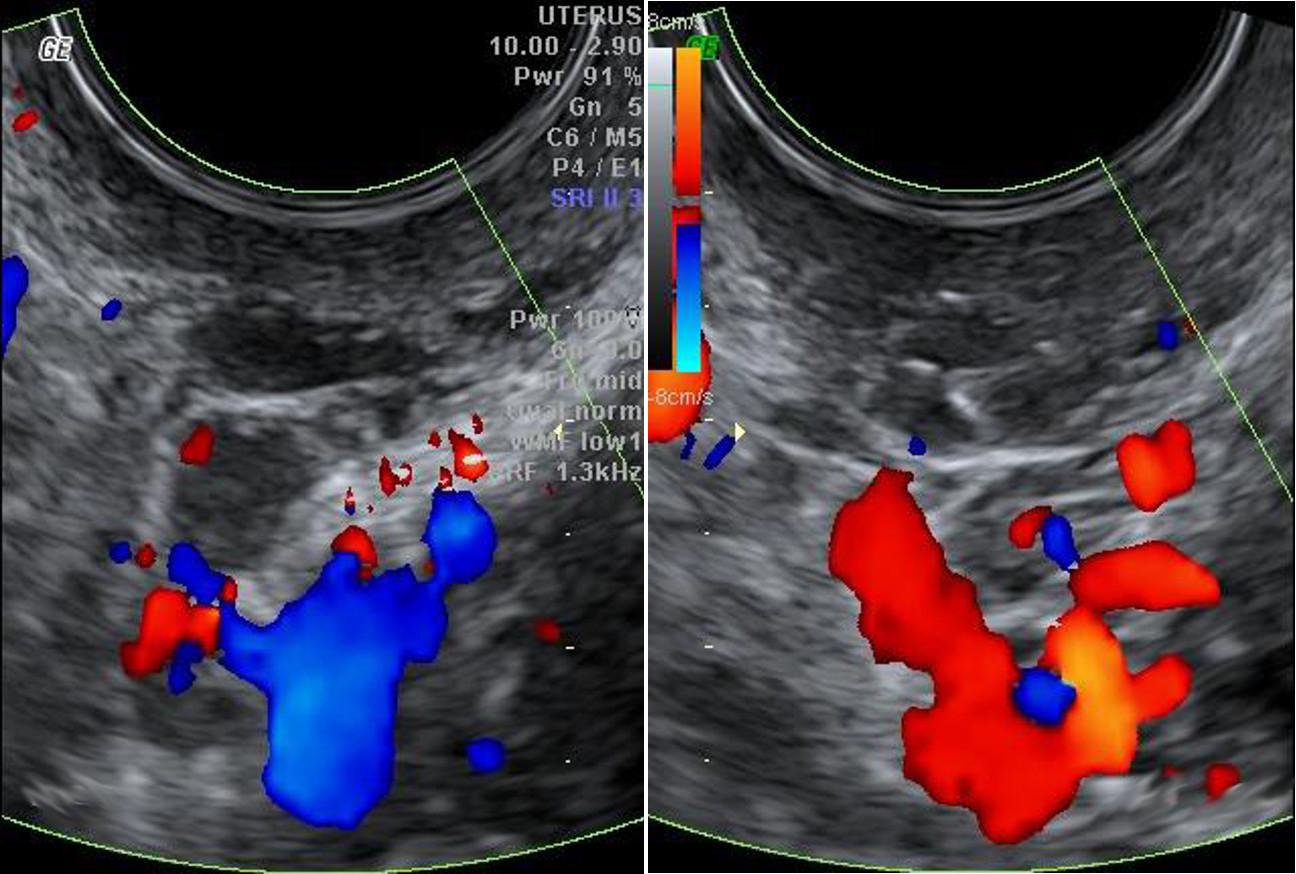

Colour with transvaginal ultrasound

Looking to get your transvaginal test done? If yes, then Evergreen Health Centre is the prominent place. We provide the colour with a TVS test at the best prices from specialized doctors. Our test is very helpful for women to look at their uterus, ovaries, fallopian tubes, cervix, and pelvis area. If you are facing any sort of abnormal pelvis, pelvis pain, vaginal bleeding, or urinal fibroids problem, our test is a must to get done. Before initiating, our radiologists will explain the process of the same to make you feel comfortable. It can be availed 24*7 with us.

• This technique involves the usage of sound waves to see inside the body and develop detailed images.